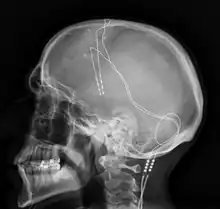

Deep brain stimulation (DBS) is a surgical procedure that implants a neurostimulator and electrodes which sends electrical impulses to specified targets in the brain responsible for movement control. The treatment is designed for a range of movement disorders such as Parkinson's disease, essential tremor, and dystonia, as well as for certain neuropsychiatric conditions like obsessive-compulsive disorder (OCD) and epilepsy.[1] The exact mechanisms of DBS are complex and not entirely clear, but it is known to modify brain activity in a structured way.[2]

Components and placement

The DBS system consists of three components: the implanted pulse generator (IPG), the lead, and an extension. The IPG is a battery-powered neurostimulator encased in a titanium housing, which sends electrical pulses to the brain that interfere with neural activity at the target site. The lead is a coiled wire insulated in polyurethane with four platinum-iridium electrodes and is placed in one or two different nuclei of the brain. The lead is connected to the IPG by an extension, an insulated wire that runs below the skin, from the head, down the side of the neck, behind the ear, to the IPG, which is placed subcutaneously below the clavicle, or in some cases, the abdomen.[8] The IPG can be calibrated by a neurologist, nurse, or trained technician to optimize symptom suppression and control side effects.[35]

DBS leads are placed in the brain according to the type of symptoms to be addressed. For non-Parkinsonian essential tremor, the lead is placed in either the ventrointermediate nucleus of the thalamus or the zona incerta;[36] for dystonia and symptoms associated with PD (rigidity, bradykinesia/akinesia, and tremor), the lead may be placed in either the globus pallidus internus or the subthalamic nucleus; for OCD and depression to the nucleus accumbens; for incessant pain to the posterior thalamic region or periaqueductal gray; and for epilepsy treatment to the anterior thalamic nucleus.

All three components are surgically implanted inside the body. Lead implantation may take place under local anesthesia or under general anesthesia ("asleep DBS"), such as for dystonia. A hole about 14 mm in diameter is drilled in the skull and the probe electrode is inserted stereotactically, using either frame-based or frameless stereotaxis.[37] During the awake procedure with local anesthesia, feedback from the person is used to determine the optimal placement of the permanent electrode. During the asleep procedure, intraoperative MRI guidance is used for direct visualization of brain tissue and device.[38] The installation of the IPG and extension leads occurs under general anesthesia.[39] The right side of the brain is stimulated to address symptoms on the left side of the body and vice versa.